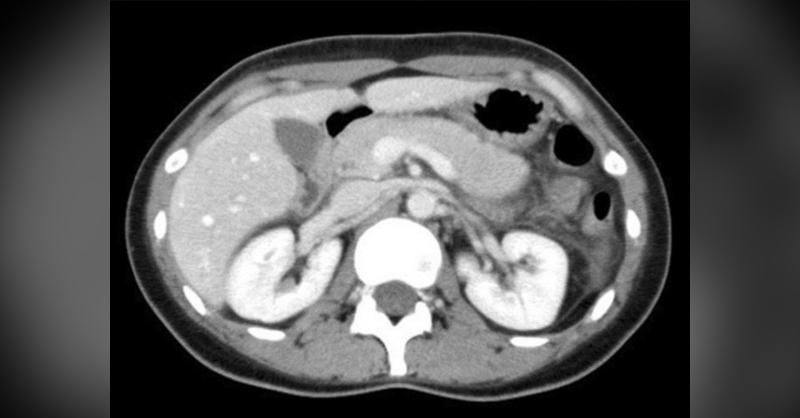

- A 31-year-old woman with Fulminant Type 1 Diabetes Mellitus

Fulminant type 1 diabetes mellitus (FT1D) is a novel subtype of type 1 diabetes. Given below are the specific clinical manifestations shown at the onset of FT1D: 1) Hyperglycemia with diabetic ketoacidosis 2) Plasma glucose level is more than 16.0 mmol/L (288 mg/dL), whereas glycated hemoglobin level is less than 8.7% 3) Urinary C-peptide excretion

A 31-year-old woman with Fulminant Type 1 Diabetes Mellitus